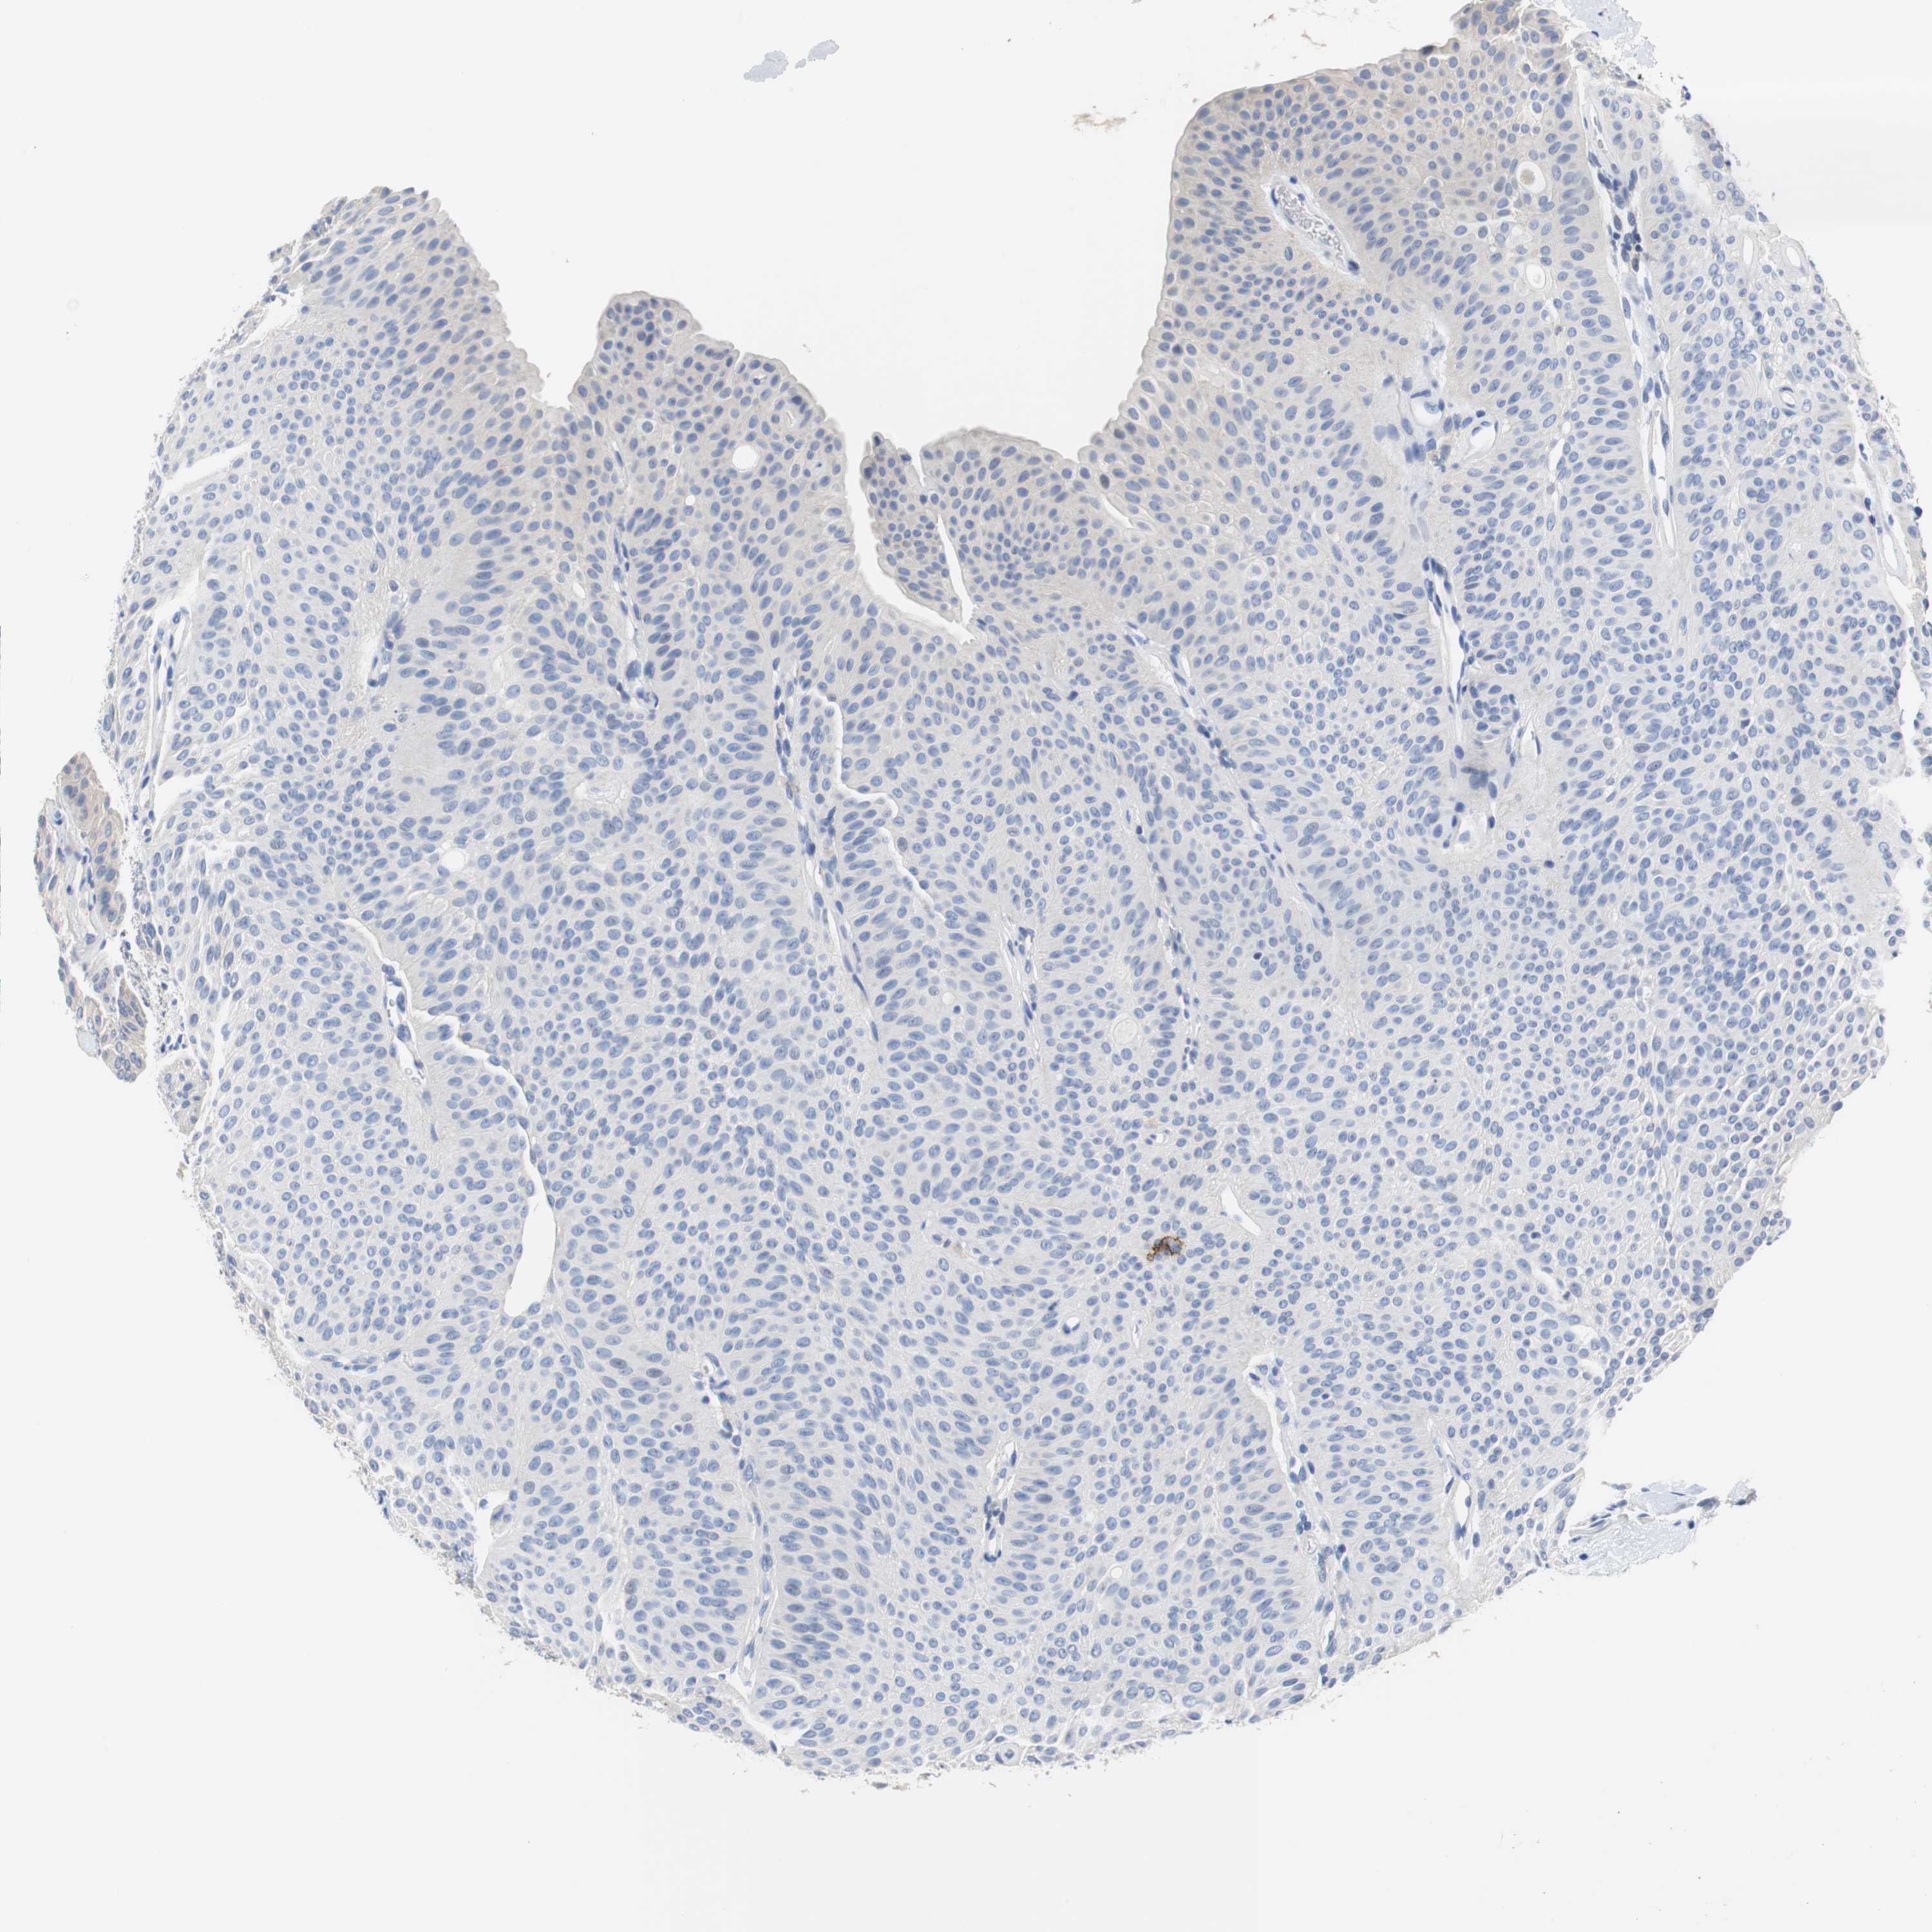

UROTHELIAL CANCER - Protein expressioni

A mouse-over function shows sample information and annotation data. Click on an image to view it in a full screen mode. Samples can be filtered based on level of antibody staining by selecting one or several of the following categories: high, medium, low and not detected. The assay and annotation is described here.

Note that samples used for immunohistochemistry by the Human Protein Atlas do not correspond to samples in the TCGA dataset.

Antibody stainingi

Antibody staining in the annotated cell types in the current human tissue is reported as not detected, low, medium, or high, based on conventional immunohistochemistry profiling in selected tissues. This score is based on the combination of the staining intensity and fraction of stained cells.

Each image is clickable and will lead to virtual microscopy that enables deeper exploration of all samples and also displays staining intensity scores, fraction scores and subcellular localization as well as patient and tissue information for each sample.

Antibody HPA006277

Antibody HPA006507

Antibody CAB017027

Staining

High

Medium

Low

Not detected

Intensity

Strong

Moderate

Weak

Negative

Quantity

>75%

75%-25%

<25%

None

Location

Nuclear

Cytoplasmic/membranous

Cytoplasmic/membranous,nuclear

Urothelial carcinoma, Low grade

Urothelial carcinoma, High grade